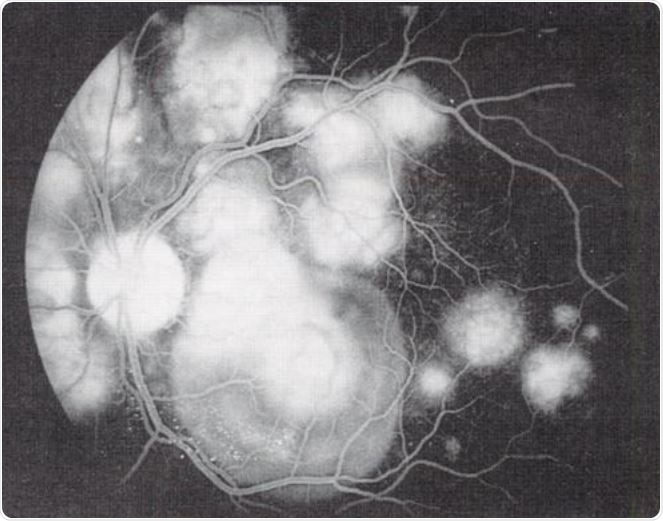

Acute Posterior Multifocal Placoid Pigment Epitheliopathy (APMPPE). Image Credit: uveitis.org

It can affect one or both eyes, and is characterized by multiple yellowish white or light-colored lesions that form in the retina.